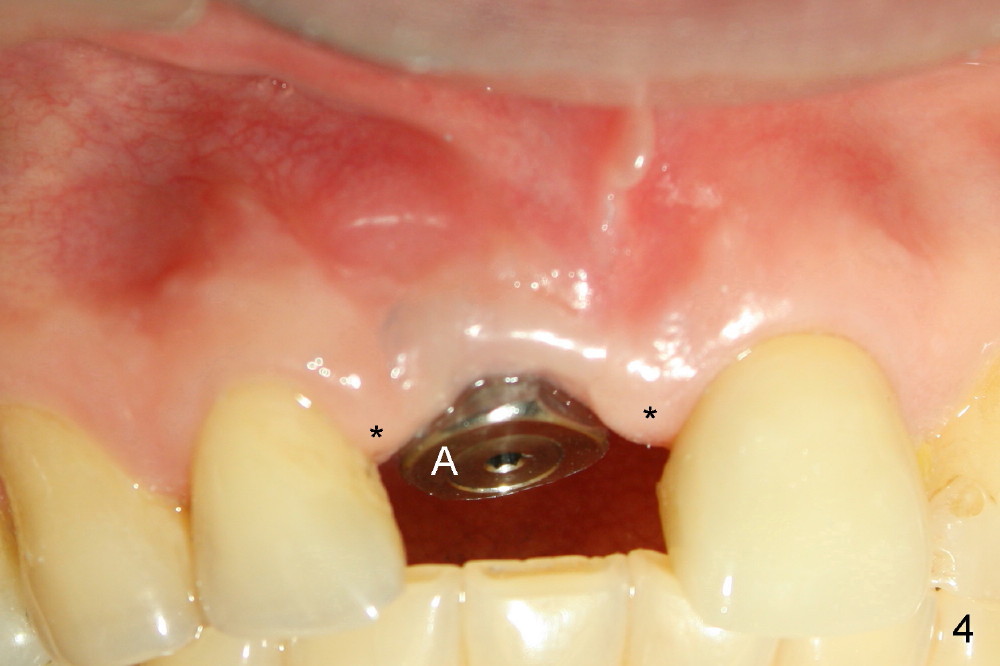

其实临床情况千变万化,处理方法可以有所变化。朱女士六十来岁,后牙缺失严重,右上中切牙根管治疗重做后感染复发(图一*:根尖阴影),但是没有任何症状,不久牙冠脱落,根尖瘘道(图二箭头)。估计炎症不是那么严重,拔牙后,常规牙槽窝处理,开始即刻植牙。处理颊侧根尖缺失办法,不是植骨,理由是植骨和植牙同时进行,增加身体负担,它们都是异物。

植牙窝适当远离颊侧根尖缺失处,植牙过程可能自行缩小,关闭缺失,最后身体自然修复。